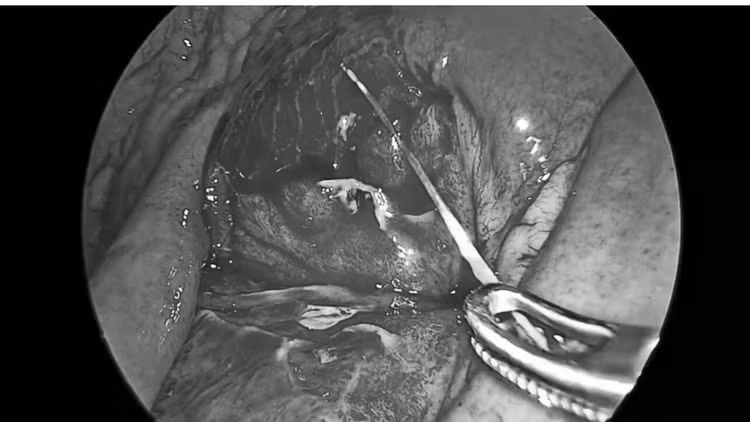

Xương cá đâm thủng ruột bệnh nhân - Ảnh BVCC

Ngay sau khi xác định chẩn đoán, bệnh nhân được chỉ định phẫu thuật cấp cứu. Ê-kíp phẫu thuật của Khoa Ngoại Tổng hợp đã tiến hành phẫu thuật nội soi lấy dị vật, xử trí lỗ thủng ruột và làm sạch ổ bụng.